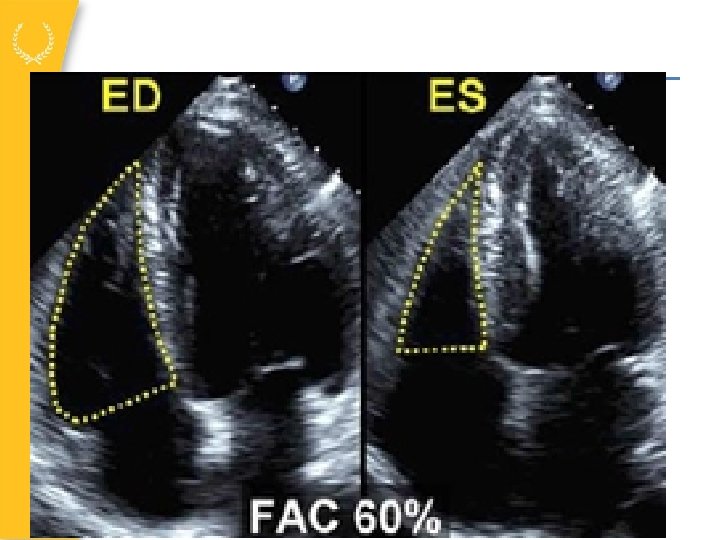

Fractional area change